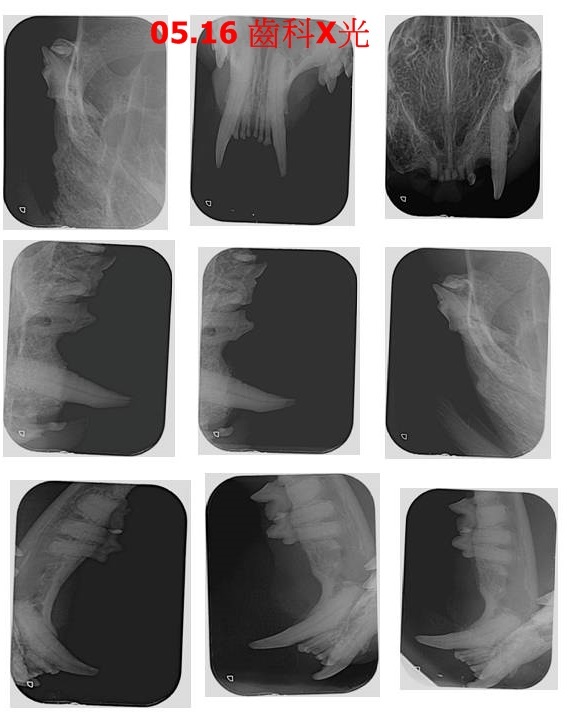

2019年4月間照護員發現阿轉食慾不佳,回報後約診檢查結果是牙齦炎及牙齒不好影響食慾,因此於5月16日進行牙周手術拔牙洗牙,拔除了左上犬齒1顆、後上小牙3顆,術後當日即接回照護。

本筆醫助是阿轉在沐恩醫院檢查治療牙周的費用,包含牙周手術、齒科X光、用藥、血檢等,請大家幫幫可愛的阿轉,謝謝。

5/16 待轉 沐恩 牙周手術

體重:3.92kg

拔除左上犬齒1顆、後上小牙3顆、犬齒皮瓣縫合一處。

前次看診,左上犬齒基底相當紅腫,今X光顯示骨頭發炎,加上牙齦已無法包覆牙齒,因此必須拔除。